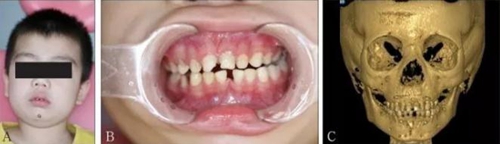

頜面部上下頜骨、顴骨及顴弓骨折、骨折片移位壓迫咀嚼肌群和下頜骨喙突,影響下頜骨的活動(dòng)而造成張口受限[10-12](圖 9、10)。

A:患者面像;B:口內(nèi)像;C:三維成像;D:全景片;E:冠狀位。

圖 9 面部外傷